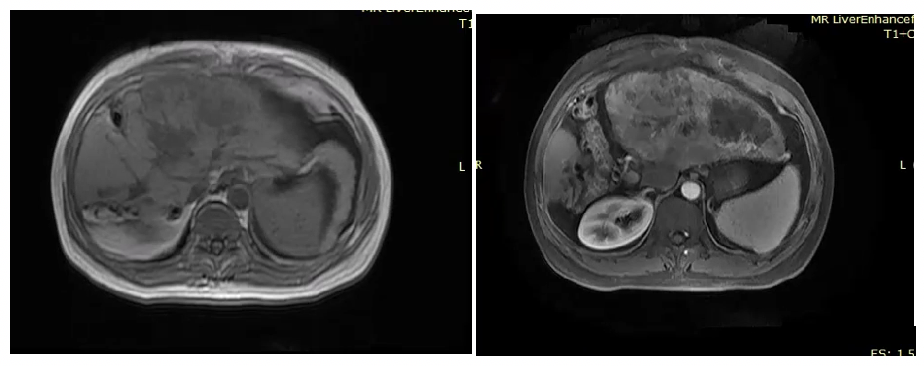

2021年11月3日MR显示,肝癌综合治疗后,病灶较前明显缩小,大小约12.2cm×8.1cm,门静脉左支癌栓;肝门区淋巴结显示;肝硬化(图6)。

图6. 2021年11月3日复查MR

复查评估显示,肝内病灶较前明显缩小,肿瘤标记物显著降低,mRECIST 标准:疾病缓解(PR)(图7)。